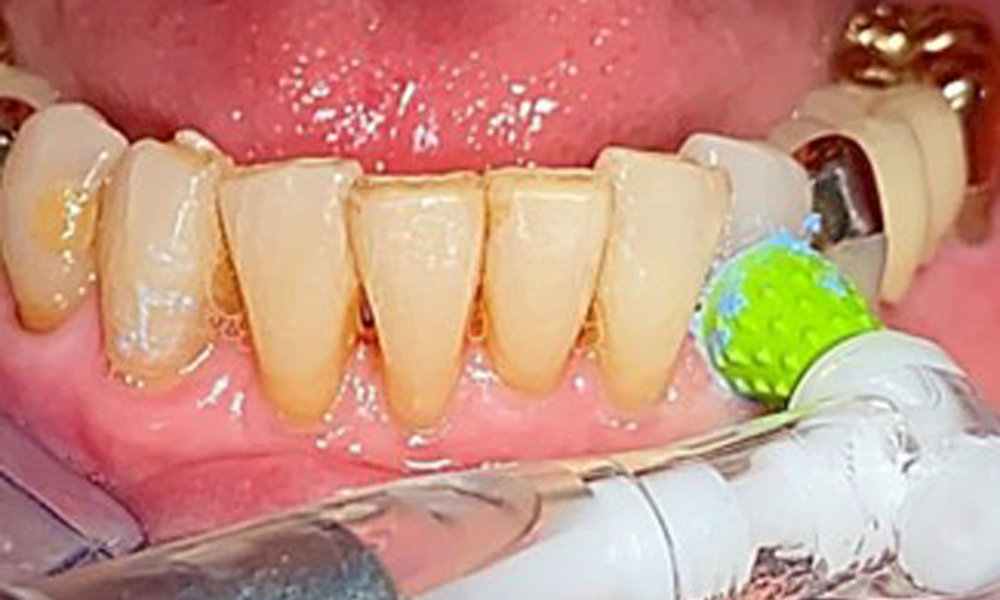

Frontal view with the maxillary denture in situ.

Fig. 1: Frontal view with the maxillary denture in situ.

The patient was fitted with a combined removable maxillary telescopic prosthesis more than 25 years ago (Fig. 1, Fig. 2, Fig. 3) and is very happy with her dentures. The patient has an adequate fixed denture for the mandible (Fig. 4).

The dental findings are as follows: Combined removable implant and tooth-supported telescopic prostheses on implants 15, 13, 21, 23, 24, 25 and tooth 11 (Fig. 1, Fig. 2, Fig. 3). The patient was fitted with a fixed mandibular denture. Adequate bridges were present over 37 to 34 and 45 to 47 (Fig. 4), the crown margins were intact and there were no active caries. A composite filling with a marginal gap was present on tooth 43. There was mandibular gingival recession, exposing 1 to 3 mm of root surface. This also applies to 11.